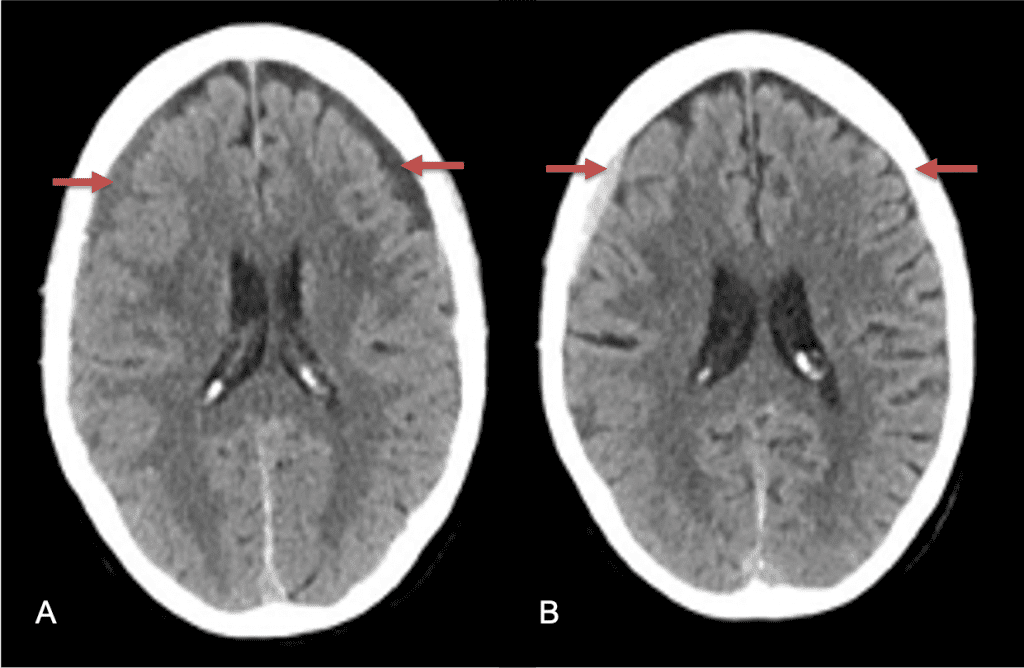

A woman in her 80s developed mild dizziness and headache following incidental trauma working in her garage one day. She presented several weeks later to the ER and was diagnosed with bilateral subdural hematomas, which were initially managed with observation, low dose Decadron, considering the mildness of symptoms, advanced age, and history of CLL with thrombocyptopenia (<100k). Over the next 4 weeks, the collections remained relatively stable with evidence of slight growth (10 to 12 mm thickness, and 2 mm right to left shift) on NCT (Figure 1. A and B).

Figure 1. A) 6 weeks post mild trauma B) 4 weeks post mild trauma demonstrates stable subacute subdural collections with mild growth and sulcal effacement.

CT follow-up at 1 week demonstrates early resorption. 2 weeks post MMA embolization, resolution of the left subdural collection with new small thin acute hemorrhage in an otherwise stable right subdural collection is observed (Figure 3. A and B).

Figure 3. A) 1 week post MMA embolization demonstrating decreasing thickness bilaterally B) 2 weeks post MMA demonstrates resolution on left, with small new acute component on right with overall decreased thickness.

Clinically, the patient improved over the few weeks with the occasional transient twinge of a headache, but resolution of dizziness. Follow-up CT at 10 weeks demonstrated complete resolution of the bilateral subdural hematomas with our patient completely asymptomatic and back to all of her activities of daily living. Considering her history of thrombocytopenia and CLL, we will continue to monitor her into the future and are excited about her progress and recovery. (Figure 4. A and B)

Figure 4. A and B) – 10 weeks following embolization demonstrates complete resolution of bilateral collections both acute and chronic.